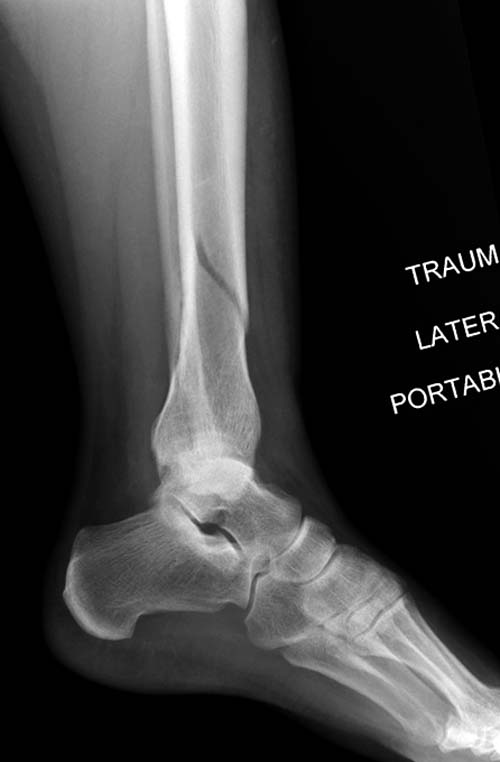

Второй случай в результате скоростной травмы, кроме пилона, вовлечение других органов! Отек при поступлении и открытый перелом на другой стороне. В таких случаях нет смысла спешить, и временный наружный фиксатор на несколько дней. После спадения отека фиксация передне-наружной пластиной. Реабилитация - ранние движения, без нагрузки.